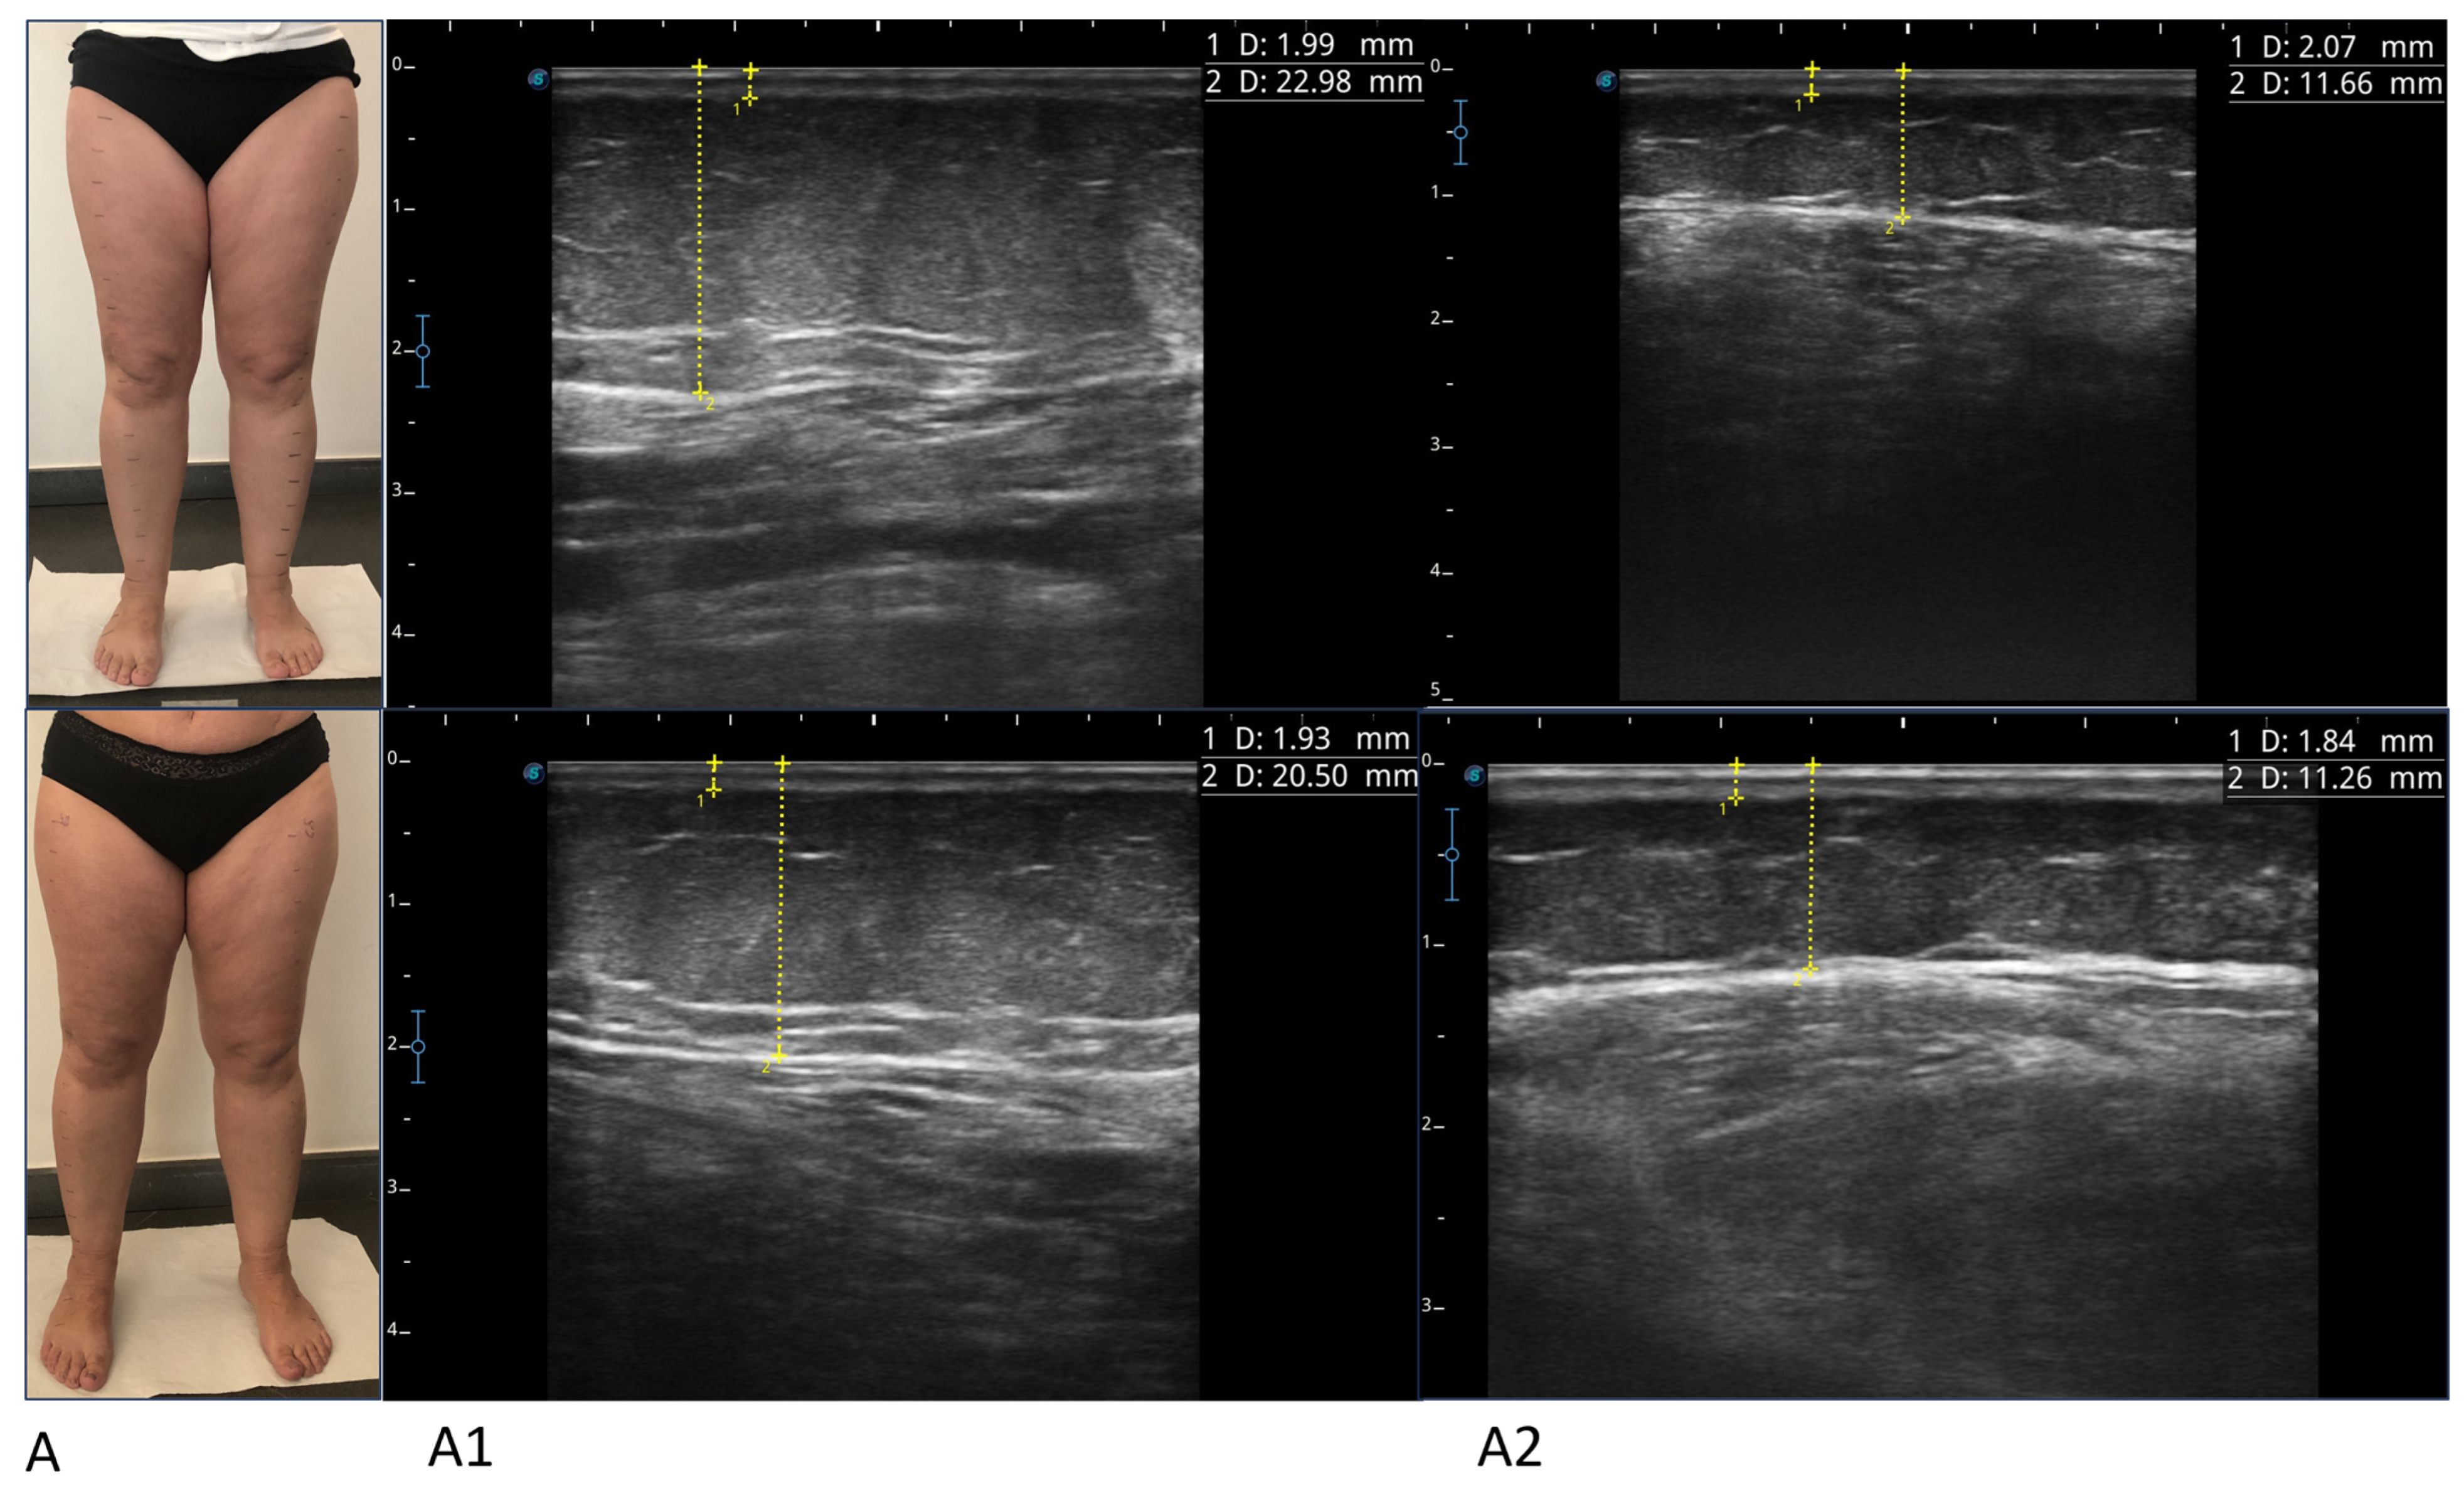

Figure 2.

Photographs and ultrasounds of two patients (A,B), before treatment (images above) and after treatment (images below). The ultrasound measurements are represented by the dashed yellow lines: the thickness of the skin was measured from the skin surface to the lower edge of the epidermis and dermis complex, and the thickness of the suprafascial superficial adipose tissue was measured from the skin surface to the subcutaneous transition structure (fascia). All imaging was performed using a high-frequency linear probe (8–14 MHz), keeping the probe perpendicular to the skin and always without applying pressure. For patient A, ultrasound images relating to the lower medial third of the leg (A1) and the upper lateral third of the leg (A2) before and after the treatment are shown (box above and box below, respectively). For patient B, ultrasound images relating to the lower medial third of the thigh (B1) and the upper medial third of the thigh (B2) before and after the treatment are shown (box above and box below, respectively).